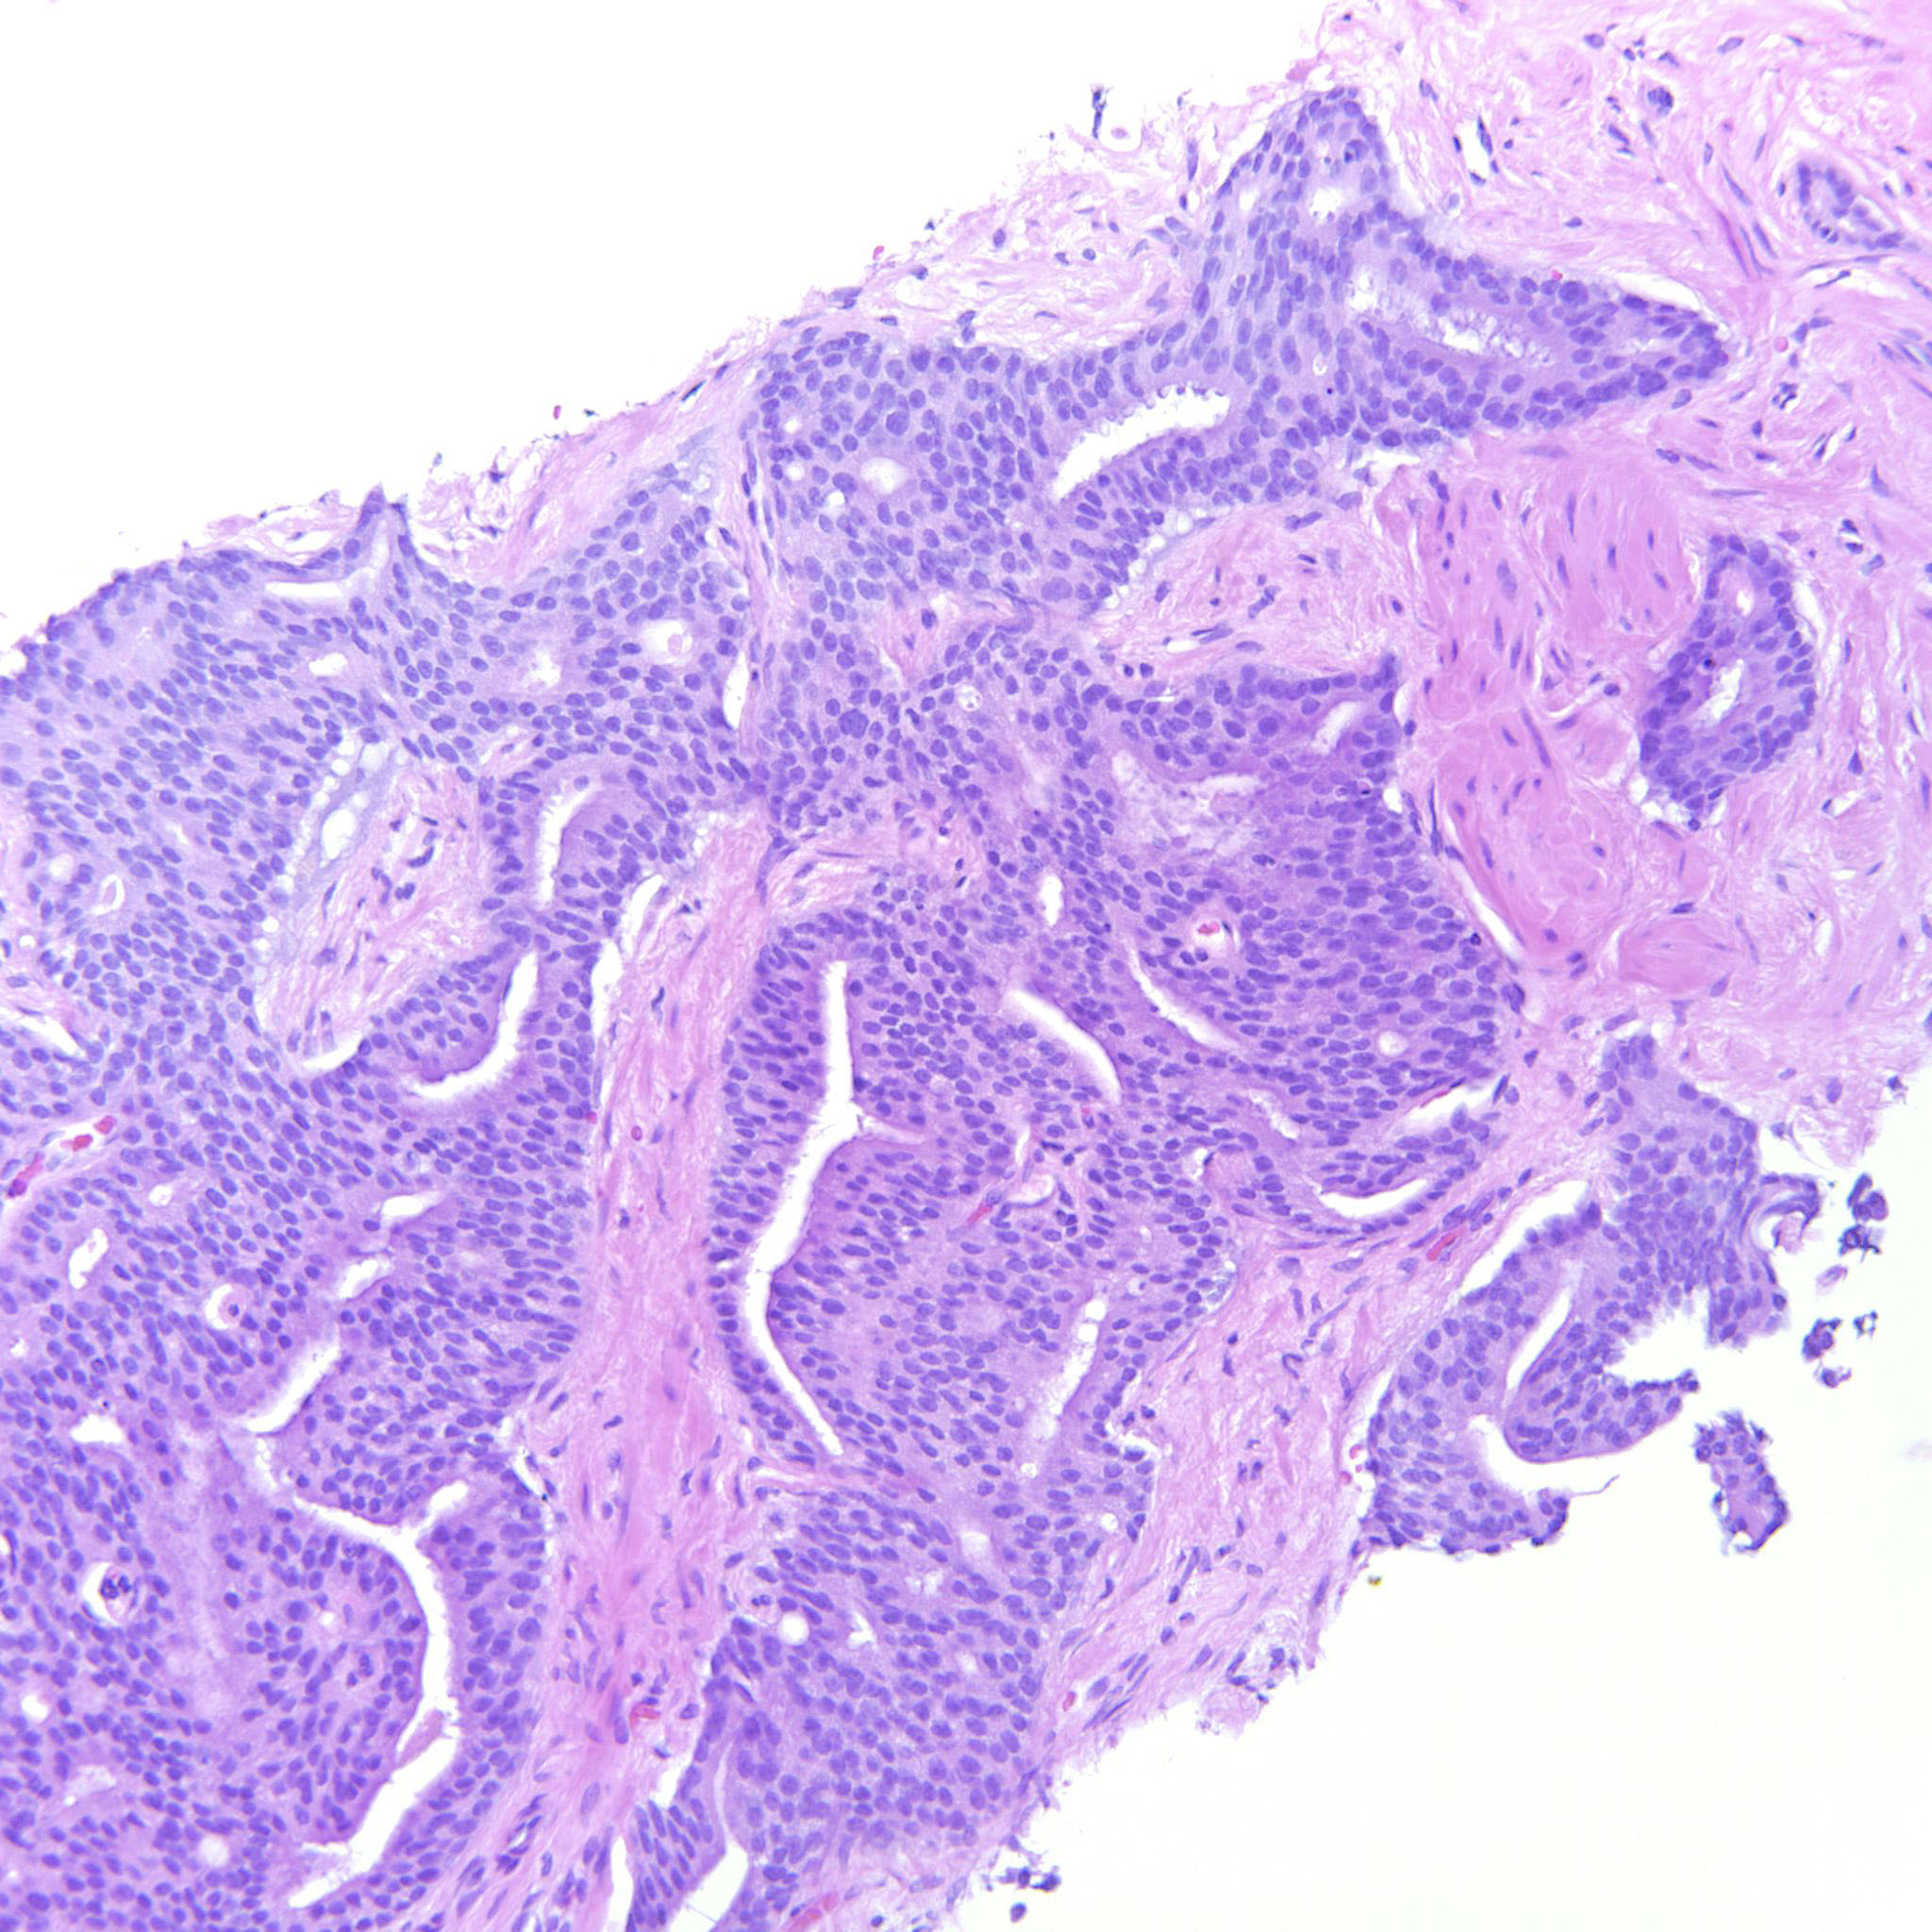

Prostate cancer grading

Case ID: 306